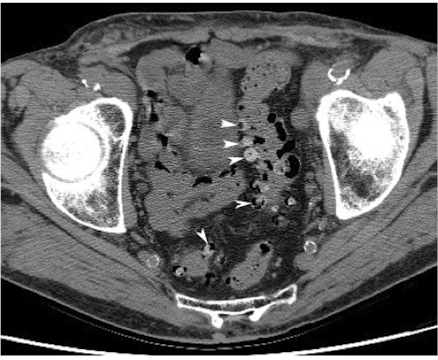

What is this and what type of scan

Diverticulosis, CT